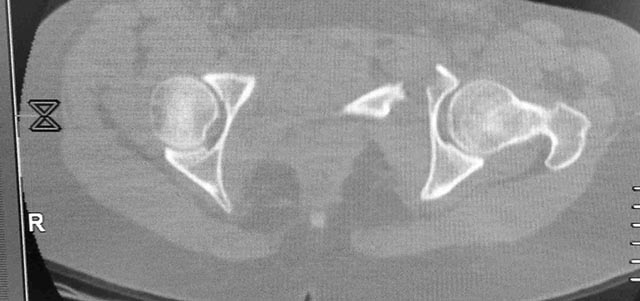

Женщина,21, социальна, без вредных превычек, сбита авто. Кожа не повреждена. Других повреждений нет. Гемодинамически стабильна. травме 2 сут. Планируем спереди открыто через Stoppa, далее сзади крестец и ость закрыто (крестец может через обе массы?). Интересует мнение по альтернативным вариантам и по предложенному (tricks and shots). Заранее благодарен.PS Только часть скринов с body scan, один с контрастированием пузыря.

Постоп. Верхняя ветвь возле шейки мочевого пузыря, нижняя так же где-то глубоко в мышцах, ротирована. Обе практически лишены кровоснабжения. лонное сочленение фактически свободно лежащее, справа почти целое, но ветви сломаны возле него. Слева часть лонного сочленения цела на 2/3. интраоперационно подвижность правой половины таза. Постоп все стабильно, но все же планирую дополнительно провести IS винт справа.